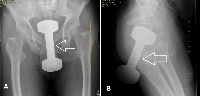

В случае перелома шейки бедра компания МосРентген Центр госпитализирует в Склиф для эндопротезирования.